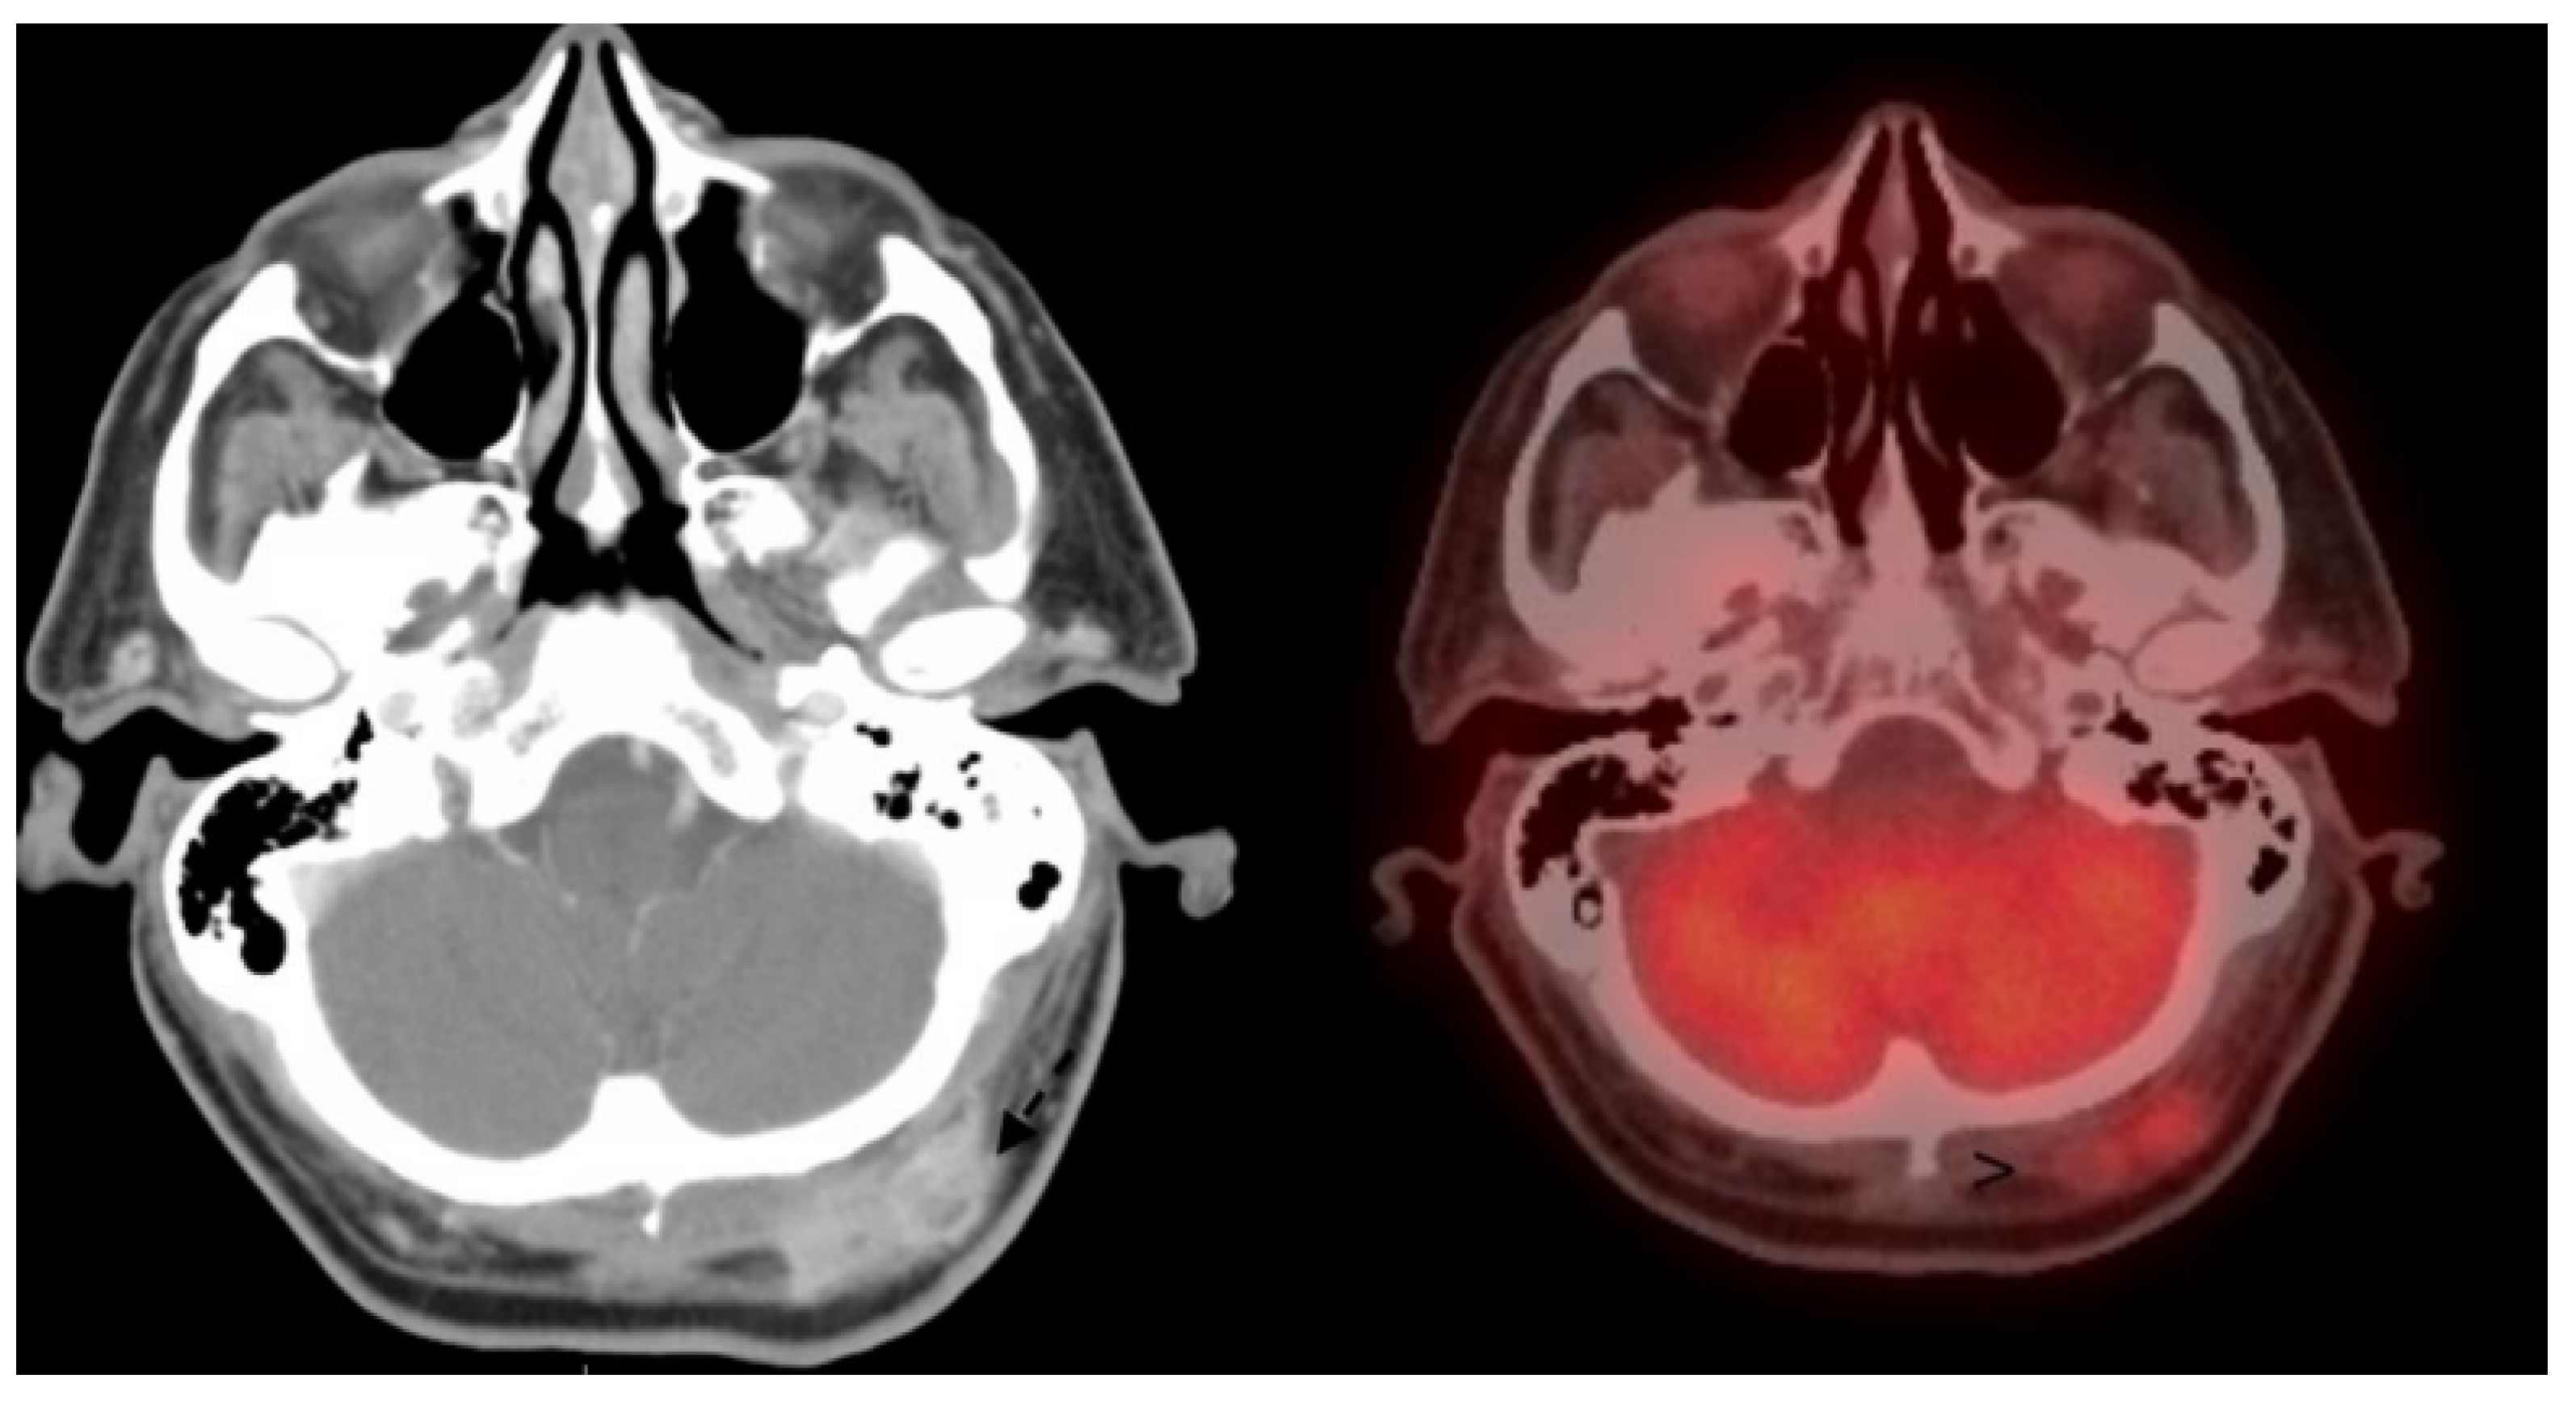

- Colgan, M.B.; Tarantola, T.I.; Weaver, A.L.; Wiseman, G.A.; Roenigk, R.K.; Brewer, J.D.; Otley, C.C. The predictive value of imaging studies in evaluating regional lymph node involvement in Merkel cell carcinoma. J. Am. Acad. Dermatol. 2012, 67, 1250–1256. [Google Scholar] [CrossRef]

- Liu, J.; Larcos, G.; Howle, J.; Veness, M. Lack of clinical impact of 18 F-fluorodeoxyglucose positron emission tomography with simultaneous computed tomography for stage I and II Merkel cell carcinoma with concurrent sentinel lymph node biopsy staging: A single institutional experience from Westmead Hospital, Sydney. Australas. J. Dermatol. 2017, 58, 99–105. [Google Scholar] [CrossRef] [PubMed]

- Hawryluk, E.B.; O’Regan, K.N.; Sheehy, N.; Guo, Y.; Dorosario, A.; Sakellis, C.G.; Jacene, H.A.; Wang, L.C. Positron emission tomography/computed tomography imaging in Merkel cell carcinoma: A study of 270 scans in 97 patients at the Dana-Farber/Brigham and Women’s Cancer Center. J. Am. Acad. Dermatol. 2013, 68, 592–599. [Google Scholar] [CrossRef] [PubMed]